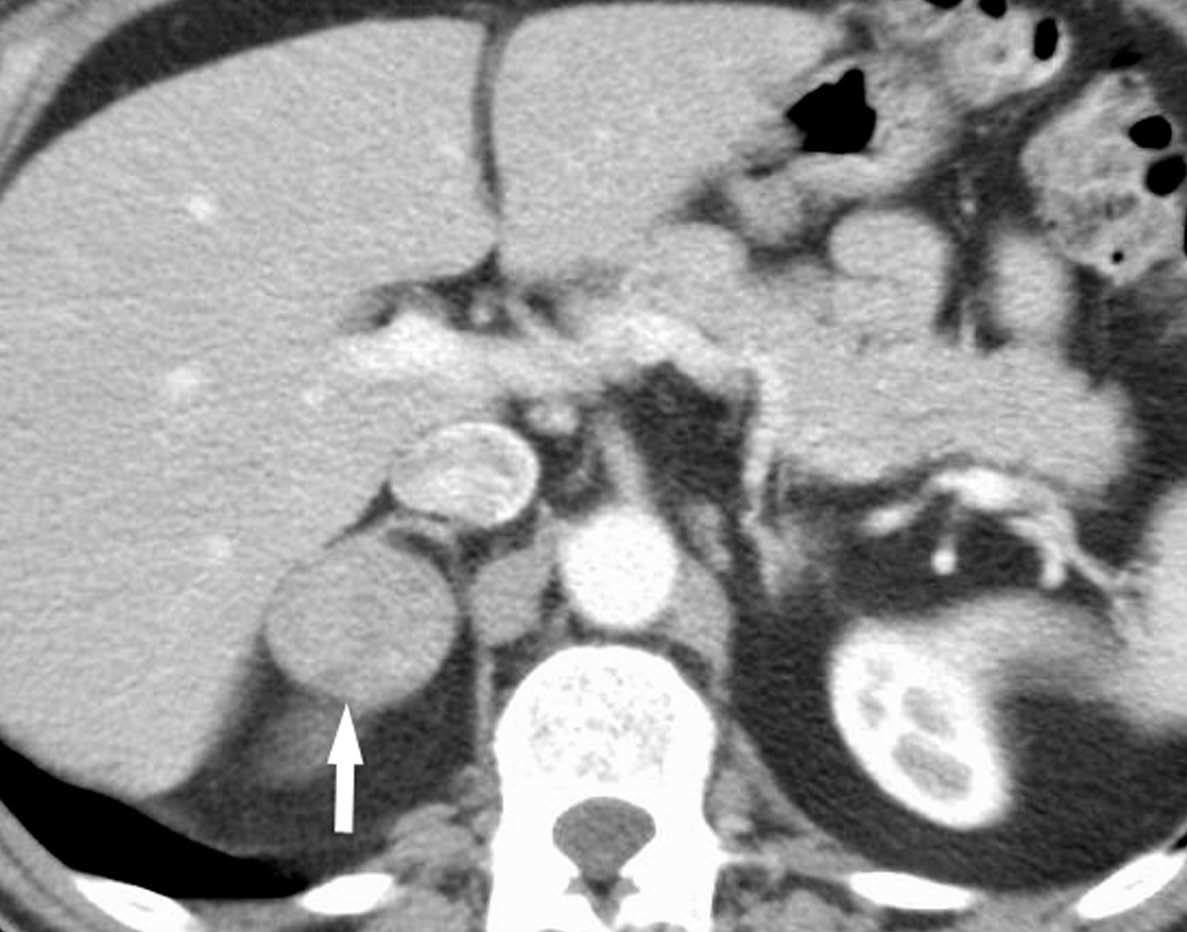

Metástasis hepáticas y suprarrenales

La aparición de nódulos suprarrenales se da en más del 10% de los pacientes con cáncer de pulmón. Dada la elevada frecuencia de adenomas benignos, es crucial la distinción entre éstos y la afectación metastásica. Ésta se puede llevar a cabo con una combinación de estrategias de imagen que incluyen TC, RM y/o PET. Por TC los adenomas suprarrenales típicamente tienen valores de atenuación bajos por la presencia de cúmulos lipídicos. Una lesión suprarrenal con valores de atenuación menores de 10 unidades Hounsfield (UH) en el estudio sin contraste, tiene una probabilidad del 98% de que se trate de una lesión benigna. Dado que ambas lesiones, adenomas y metástasis captan contraste, la valoración rutinaria de la captación no es útil en la diferenciación entre benignidad y malignidad. Si se detecta durante la realización de la TC, realizar cortes tardíos a los 15 minutos de la administración de contraste es importante, ya que si existe un lavado del contraste de más del 50% el diagnóstico de adenoma tiene una sensibilidad del 98% y una especificidad que oscila entre el 92 y el 100%20. La RM con secuencias de desplazamiento químico en la valoración de nódulos suprarrenales tiene una especificidad del 100% para el diagnóstico de adenoma (fig. 14). Sin embargo, la sensibilidad depende de la densidad de la lesión en el estudio con TC, ya que cuanto mayor es la densidad en la TC menos señal perderá en la RM, con lo que resulta más difícil etiquetarlo como adenoma21. La PET presenta una sensibilidad alta en la detección de metástasis suprarrenales, ya que cuando una lesión suprarrenal no muestra signos concluyentes en la TC de benignidad, la ausencia de actividad con la PET hace muy probable dicho diagnóstico. En los casos en que persistan dudas diagnósticas se debe recurrir a la biopsia de la lesión adrenal, especialmente si de este diagnóstico depende el manejo del paciente.

Fig. 14.--Lesión suprarrenal. (A) Tomografía computarizada (TC) abdominal sin contraste que muestra un nódulo suprarrenal derecho de baja atenuación y contornos bien definidos (flecha). (B) Con contraste se aprecia captación del mismo. (C) Resonancia magnética (RM) en fase en la que se identifica el nódulo suprarrenal isointenso con el hígado. (D) En la RM fuera de fase, se pone de manifiesto la pérdida de señal (marcadamente hipointensa con respecto al hígado) característica de estos tumores suprarrenales debido a su contenido lipídico.